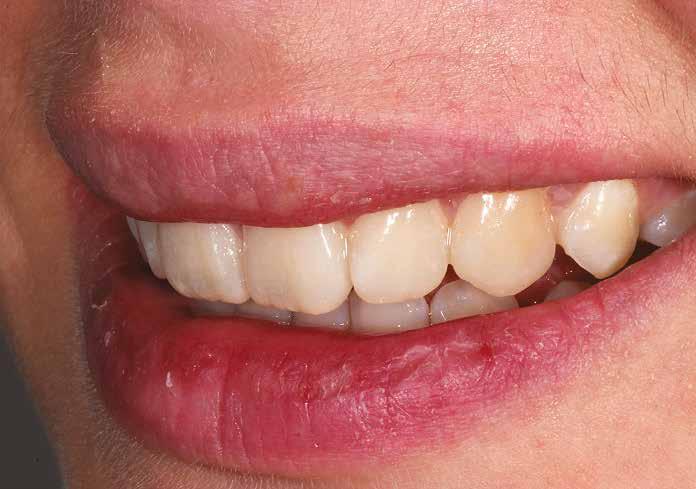

A kezelés során az jelentette a legnagyobb kihívást, hogy a héjakkal ellátott fogak élethűen utánozzák a természetes fogazat megjelenését. A fogpótlás színének, valamint a restaurátumok felszíni textúrájának és alakjának harmonikusan kell a páciens arcesztétikájához és karakteréhez illeszkednie.

A tényleges protetikai ellátás megkezdése előtt a páciens mosolygás közben látható fogait otthoni fogfehérítés keretei között a kérésének megfelelő A1-es fogszín eléréséig fehérítettük. A fehérítés során a későbbiekben héjakkal ellátásra kerülő fogak színén nem változtattunk. A fogak előkészítése részeként csupán a két felső nagymetsző (1.1,2.1) incizális élét kellett kismértékben redukálni. A többi felső front fog (1.3,1.2,2.2,2.3) nem került preparálásra.

A héjak átadását követően kialakuló állapot valósághű módon történő bemutatása érdekében próbapasztát alkalmaztunk (Try-In-Paste; Variolink® Esthetik Try-In-Paste, Ivoclar Vivadent) (11. ábra). A próba során ellenőrizzük a héjak színét, formáját és transzparenciáját. A próbapaszta alkalmazásának egyik lényeges pontja, hogy a paszta színe egyezzen meg a végleges beragasztás során alkalmazni kíván ragasztóanyag színével. A héjak végleges rögzítése során mindig adhezív rendszereket használunk.

nak megfelelően – előkészítjük (orthofoszforsavval történő savazás, lemosás, szárítás és bond réteggel történő fedés). Ezzel egyidejűleg a ragasztásra kerülő héjak is előkészítésre kerülnek (hidrofolysavval történő savazás, lemosás, szárítás, szilanizálás, bond réteggel történő fedés, és végül az alkalmazni kívánt ragasztóanyag felvitele). Ezután a héjakat a fogak felszínén egyesével pozicionáljuk, majd néhány másodpercen keresztül polimerizációs lámpa segítségével megvilágítjuk. Ezt követően a kifolyó ragasztófelesleget eltávolítjuk, majd elvégezzük a restaurátumok végső polimerizálását. A héjak végleges rögzítését követően az esetlegesen visszamaradt ragasztómaradványok eltávolításra kerülnek, valamint ellenőrizzük az okklúzió és artikuláció közben létrejövő fogérintkezéseket. Az optimális esztétikai eredmény biztosítása érdekében kiemelt jelentősége van a papillák helyreállításának (rózsaszín esztétika). A modern fogorvoslás egyik kiemelt célja a fehér- és rózsaszín esztétika közti harmonikus egyensúly megteremtése. A papillák színe, nagysága és szimmetrikus megjelenése meghatározó szerepet tölt be a rózsaszín esztétika kialakításában. Az íny lefutása ugyancsak rendkívül jelentős mértékben befolyásolja a páciens fogazatának esztétikus megjelenését.

A cikkünkben bemutatásra kerülő eset ellátása során preparációt nem igénylő héjak készítése mellett döntöttünk. A héjak készre vitele során a platinafólia technikát alkalmaztuk. Annak ellenére, hogy az elkészítésre kerülő héjak rendkívül vékonyak, és ezáltal a végleges rögzítésük előtt jelentős törésveszéllyel állunk szemben, összességében mégis olyan minimál invazív kezelési eljárásnak számítanak, amely segítségével kifogástalan esztétikai eredményeket lehet elérni. A fent leírtak alapján bátran javasoljuk e módszer alkalmazását.